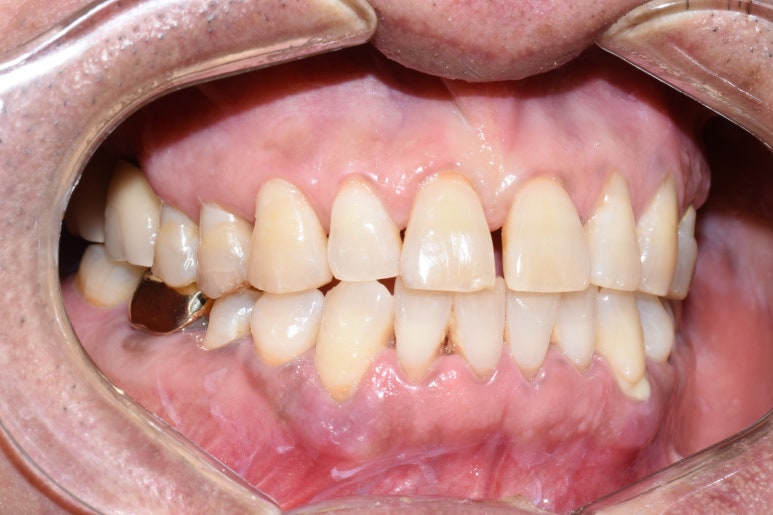

오랜 시간 치아가 방치되어 아래 파노라마와 같은 모습이었습니다.

큰 위쪽 어금니는 3개가 없고 하나는 매우 흔들리는 상태,

아래쪽 큰 어금니는 파절되고 썩어있는 상태였습니다.

↑치료 전 사진입니다. 큰 어금니 쪽에 치아들이 성하지 않아

씹기가 힘든 상태입니다.